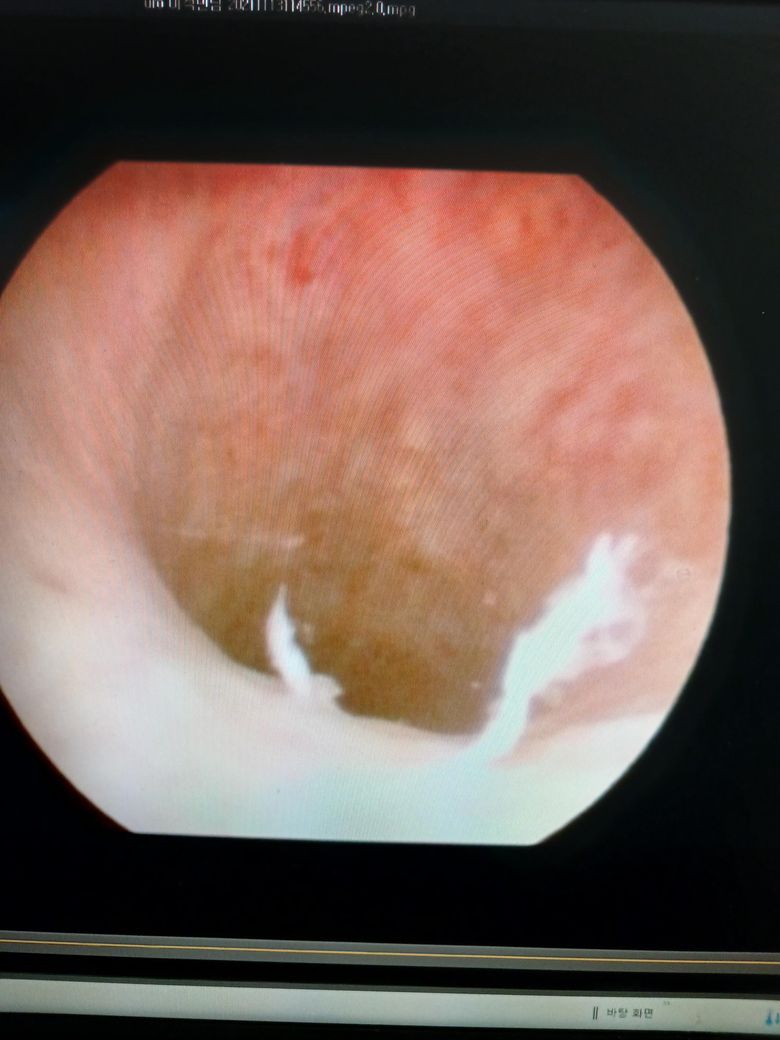

제가 사진을 보내준다고 했는데 사진을 보내 드리지 못했습니다. 방광 내시경을 했는데 껍질이 좀 벗겨 나갔습니다. 껍질이 벗겨 나간 부위에 만약에 이물질이 붙어? 있다면 소변으로 나올 수

제가 알고 싶은 것은 껍질이 나간 엠브이에 이물질이 달라붙으면 그 이물질이 함께 굳어질 수가 있는지요제가 알고 싶은 것은 껍질이 나간 MV에 이물질이 달라붙으면 그 이물질이 함께 굳어질 수가 있는지요.

이물질제가 알고 싶은 것은 껍질이 나간 부위에 이물질이 달라붙으면 그 이물질이 함께 굳어질 수가 있는지요.

방광은 일반적으로 소변만 들어있습니다. 벗겨진 점막에 이물질이 붙어있을 수 없습니다.

벗겨진 상태의 점막은 소변으로 정상적으로 배출이 됩니다.